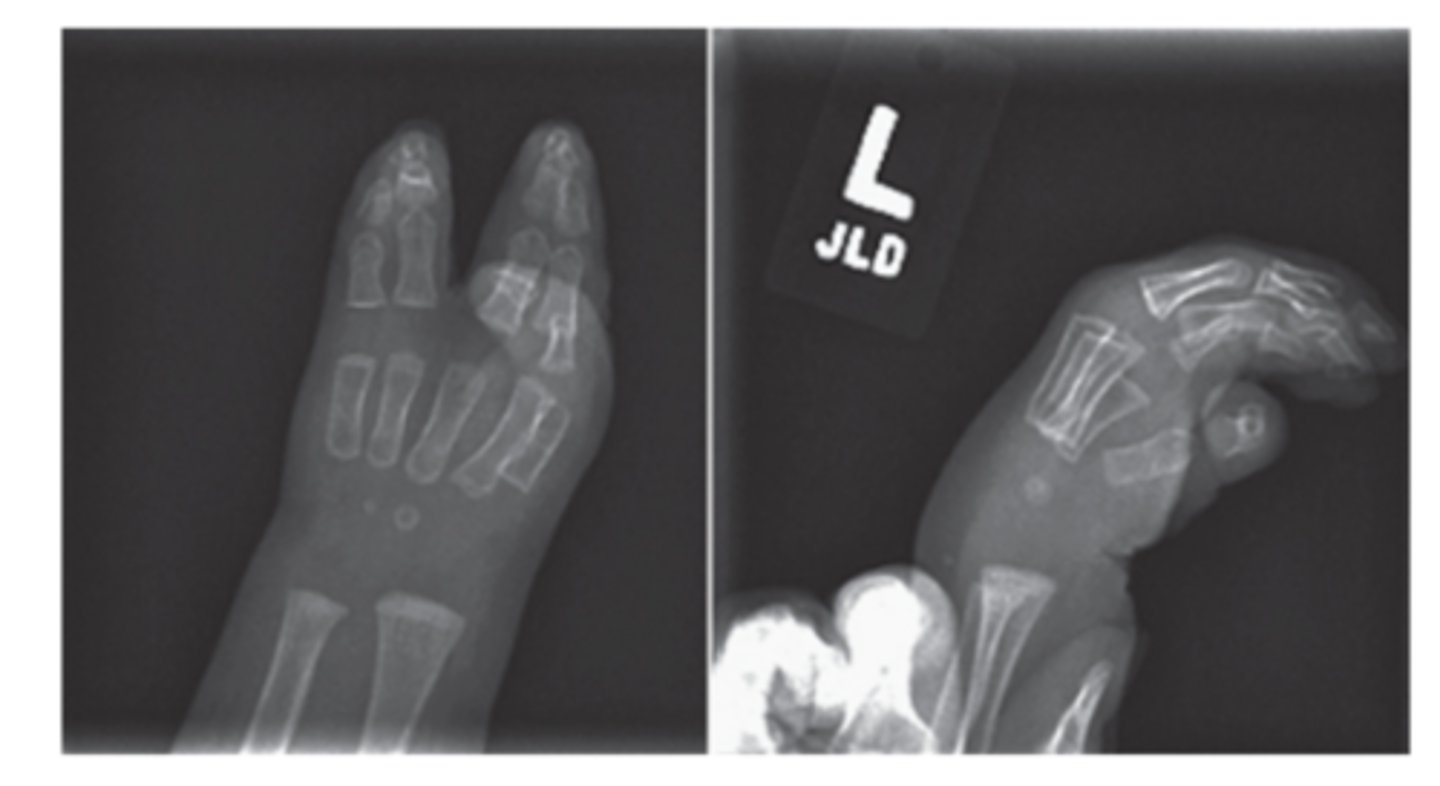

Polydactyly definition

presence of an extra digit or digits

polydactyly